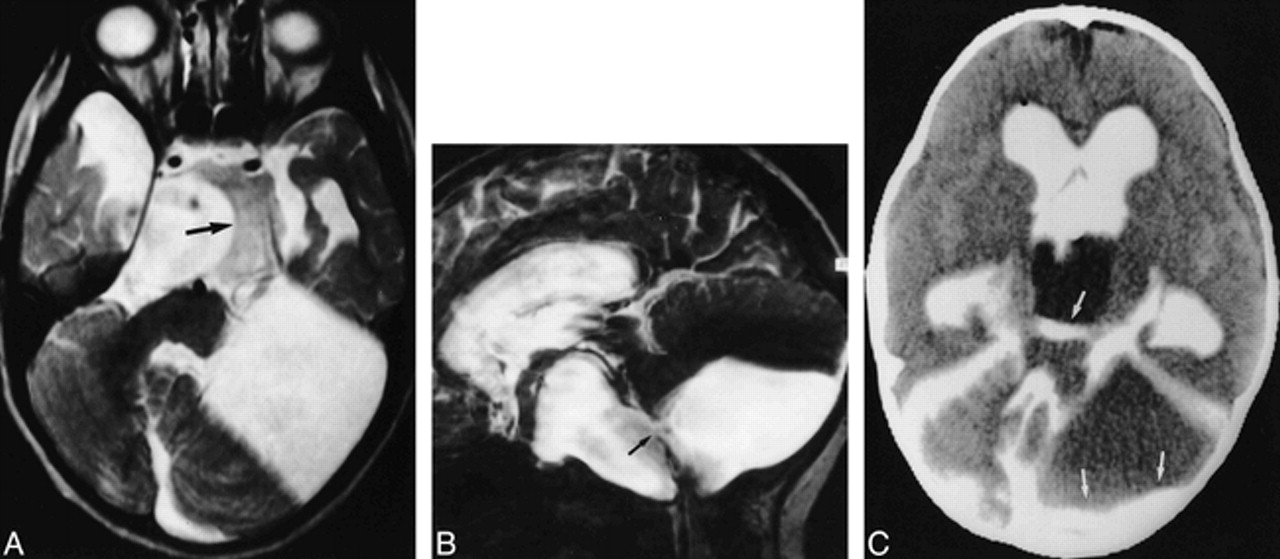

19-year-old woman with incidentally found arachnoid cysts in the cerebellopontine angle.

A, Transverse T2-weighted SE image (2000/80/1) shows high signal intensity within the enlarged cerebellopontine angles (arrows) and in the prepontine cistern. The shape of the enlarged CSF space suggests arachnoid cysts.

B, On the corresponding SSFP image (20/25/1), signal attenuation due to CSF flow is found in the prepontine cistern and fourth ventricle (curved arrows). Persistently high signal intensity is found in the cerebellopontine cysts (straight arrows) due to stationary CSF, confirming the diagnosis of arachnoid cysts.

C, Sagittal T1-weighted SE image (500/12/2) with suspected thin membrane (long arrow) between the isointense subpeduncular space (curved arrow) and the left cerebellopontine mass (short straight arrow).

D, Corresponding sagittal SSFP image (500/12/2) shows functional separation of the hypointense pulsating CSF between the temporal bone and the cerebellar peduncles (curved arrow) and the hyperintense stationary CSF within the cyst (straight arrow).